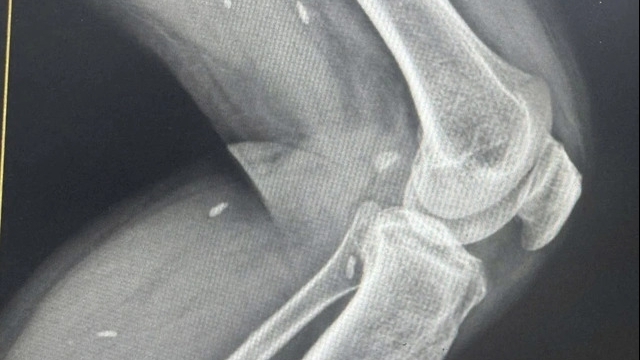

| Điện tim của bệnh nhân ngay khi được cắt đốt điện sinh lý thành công |

Sau nhiều cú sốc điện nhằm chuyển nhịp tim vẫn không đáp ứng, nam bệnh nhân được gấp rút chuyển đến Bệnh viện Chợ Rẫy. Khi người bệnh đang trên đường chuyển viện, hình ảnh về các cơn rối loạn nhịp cũng được các bác sĩ tại Bến Tre chuyển trực tiếp qua internet đến Chợ Rẫy để giúp các đồng nghiệp nắm bắt tình huống sớm trong lúc tiếp nhận bệnh nhân khi vào viện.

Tại Chợ Rẫy, sau khi được hội chẩn với tổ chuyên gia điều trị các rối loạn nhịp nhanh từ khoa Điều trị Rối loạn nhịp, bệnh nhân nhanh chóng được sắp xếp lịch trình để thăm dò và cắt đốt điện sinh lý cấp cứu. Đây là kỹ thuật xâm lấn tối thiểu, ít gây tổn thương và không để lại sẹo trên người bệnh. Sau gần 2 giờ căng thẳng, bệnh nhân nhanh chóng qua được cơn nguy kịch. Một ngày sau can thiệp, bệnh đã được xuất viện.